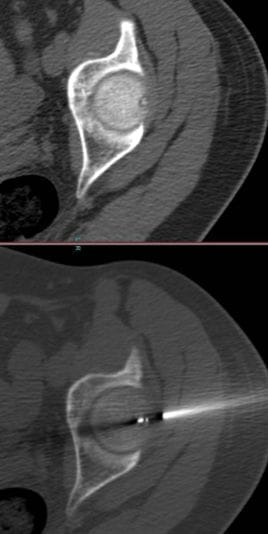

Ablația cu radiofrecvență pentru osteoid osteom se remarcă ca o tehnică minim invazivă. Această procedură este o metodă de tratament eficientă, care asigură confortul pacientului și accelerează procesul de recuperare. Pacienții revin, de obicei, rapid la activitățile lor normale după procedură. Intervenția se efectuează în condiții sterile, iar poziționarea pacientului este ajustată conform stării acestuia. Generatorul de radiofrecvență și tehnologia CT joacă roluri critice în succesul tratamentului, iar pașii procedurii sunt planificați și executați cu mare atenție.

Localizarea leziunii și calea de acces:

- Localizarea exactă a leziunii este determinată cu ajutorul scanării CT.

- Reconstrucțiile multiplan sunt utilizate pentru a stabili calea optimă de acces.

- Se acordă atenție pentru a nu afecta vasele de sânge și nervii.

Plasarea cateterului de acces:

- Un cateter de acces cu ac interior este introdus de-a lungul traiectoriei stabilite.

- Poziționarea corectă a cateterului este verificată cu noi imagini CT.

Penetrarea osoasă și electrodul de ablație:

- Un ac Kirschner este introdus în os cu ajutorul cateterului.

- Distanța până la centrul tumorii este calculată cu precizie.

- Electrodul este înlocuit cu acul Kirschner și poziția corectă este confirmată.

Inițierea ablației cu radiofrecvență:

- După conectarea electrodului la generatorul RF, începe procesul de ablație.

- Leziunea este încălzită la temperatura și pentru perioada stabilite.

- Temperatura și durata sunt cruciale pentru o ablație optimă.

Monitorizarea post-procedurală:

- O scanare CT finală este efectuată pentru a verifica eventualele leziuni ale țesuturilor moi.